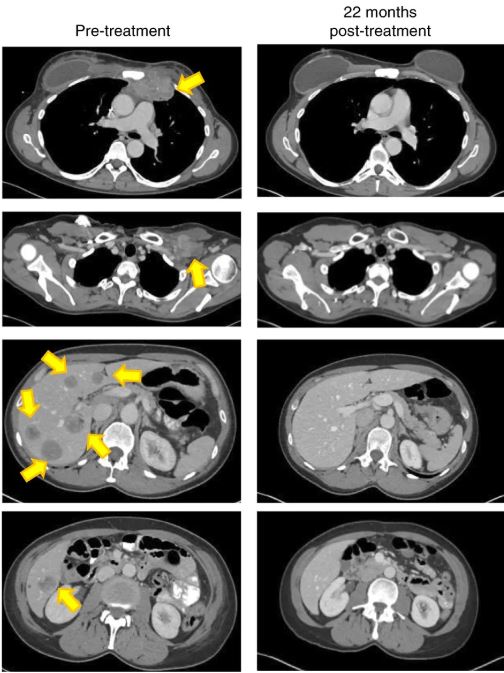

Предлагаю фрагмент рисунка 2d из оригинальной статьи. Даже впервые видящим томограмму будет очевидно, что все отмеченные желтыми стрелками посторонние включения исчезли.

судя по графику, за шесть недель полностью исчезли только самые маленькие (около двух см), большие исчезали дольше от 18 до 48 недель